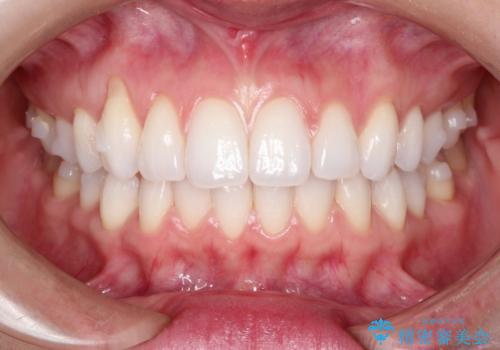

八重歯をマウスピース矯正で治療し、レーザーホワイトニングを行った症例

- 主訴:「右上犬歯を引っ込めて、歯並びをキレイにしたい」

右上の八重歯を気にされてご来院されました。結婚式を控えていたため挙式にまでに可能な限りキレイにしたいとのことでした。

また、ホワイトニングも一緒にご希望されたため、挙式のタイミングに合わせてレーザーホワイトニングを施術させていただきました。

右上の犬歯の歯茎は矯正前から退縮を起こしていましたが、矯正後もその退縮に関しては変化がありませんでした。今回は患者様が歯肉退縮に関しては治療をご希望ではありませんでしたが、当院ではこのように歯茎が下がり露出した根面を、歯茎を移植することでカバーし見た目を改善する手術を行っています。